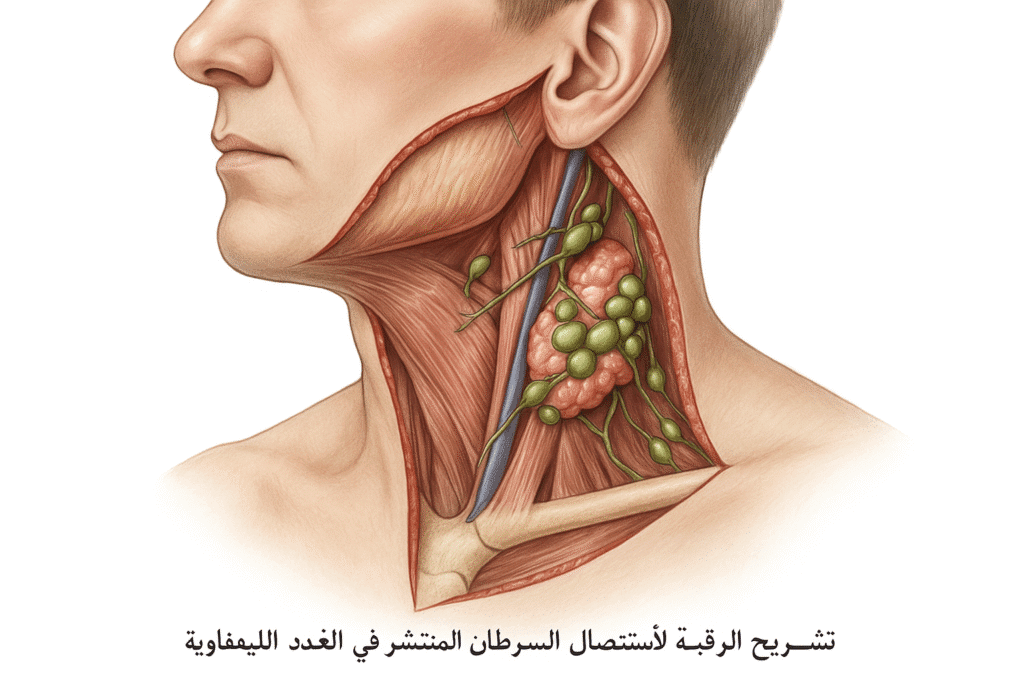

أطباء الأورام والسرطان

50 listings